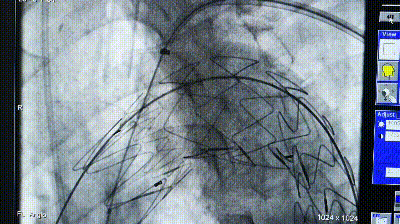

导丝破膜,各角度反复确认

机械破膜和激光破膜

破膜装置开窗

转播手术过程中即便熟练团队开窗,时间不可控,导丝穿破FUSTAR